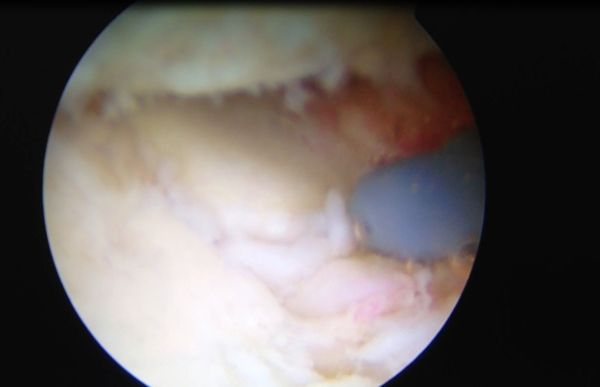

一般来说:1、针对疾病早期的患者,我们一般推荐休息、口服非甾体消炎药、理疗、康复治疗。2、针对保守治疗三个月效果欠佳的患者,我们一般根据患者的具体情况采用肘关节关节镜镜微创手术或小切口切开手术的方法来为患者解决问题。有的患者我们采用人工肘关节置换手术的方法帮助患者解决肘关节伸屈受限的问题。3、我们非常重视手术后的康复治疗。我们有专门的骨关节康复师和肘关节手术后全套的康复方案帮助患者早日康复。

上图:高绪仁医学博士、博士后、副主任医师、副教授在为肘关节僵硬、伸不直、屈不下来的患者进行肘关节关节镜微创手术治疗。